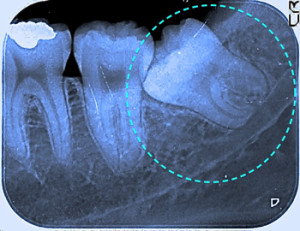

斜めに生える親知らず 神経を巻き込む

コラム「斜めに生える親知らず 神経を巻き込む」の画像